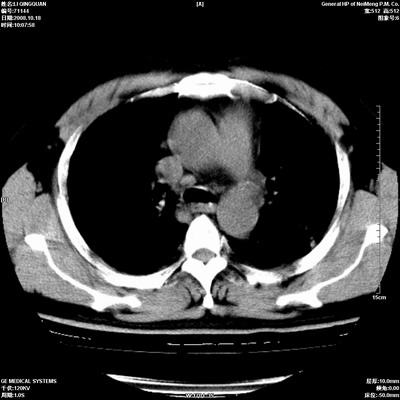

以下是引用duguo在2008-10-19 13:59:00的发言:[br]左肺上叶支气管狭窄,首先考虑中心型肺癌伴阻塞性肺炎\\肺不张.

以下是引用ybing在2008-10-19 12:58:00的发言:[br]左肺上叶阻塞性炎症-建议支气管镜进一步检查除外中央型肺癌

以下是引用随光逐影在2008-10-19 14:31:00的发言:[br]考虑左肺中央型肺癌并左肺上叶阻塞性肺炎,肺不张。